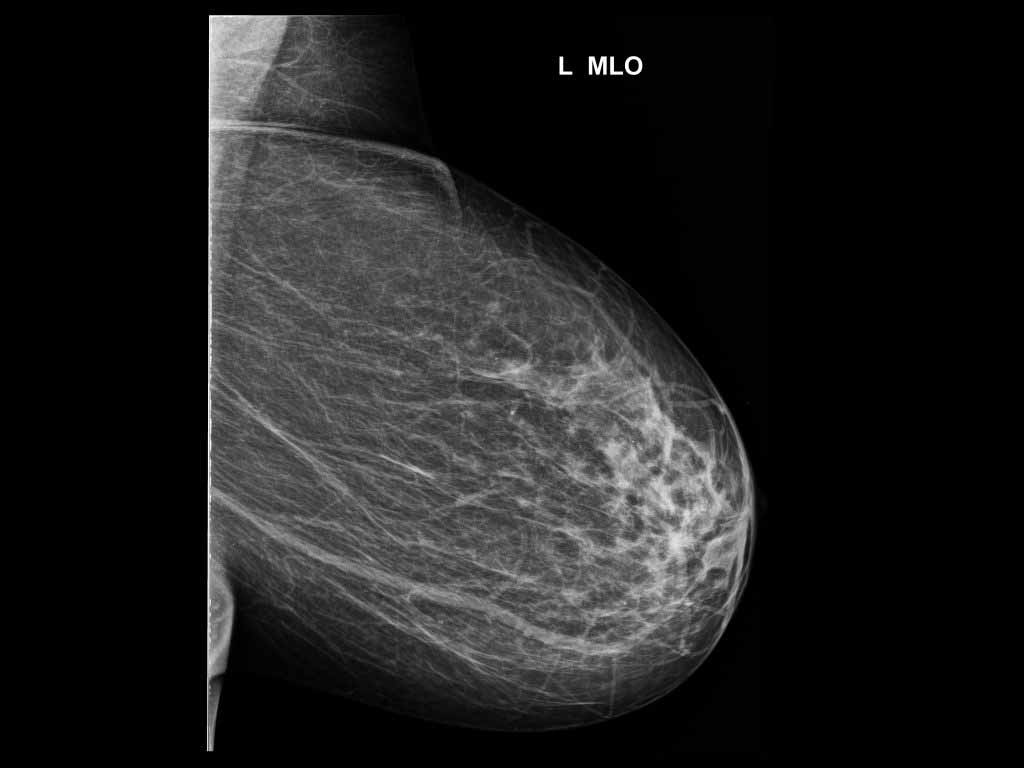

Kesesuaian Kategori Bi Rads Mamografi Dengan Pemeriksaan Histopatologi Di Rs Kanker Dharmais Tesis Pdf Download Gratis

Http Lib Ui Ac Id File File Digital 20367141 Sp Yulia 20rachmawati Pdf

Http Lib Ui Ac Id File File Digital 20367141 Sp Yulia 20rachmawati Pdf

Bab 2 Ca Mammae